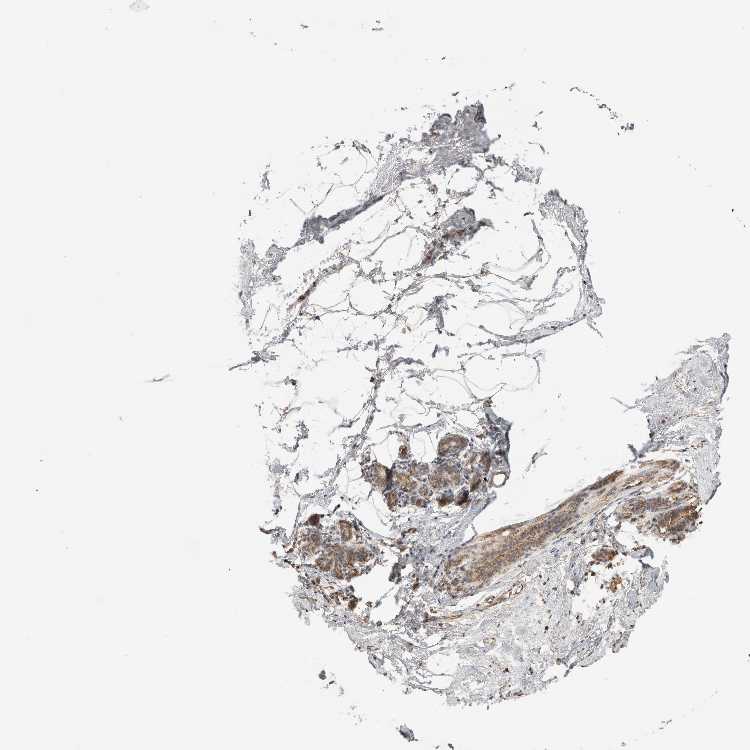

BREAST - Antibody stainingi

Antibody staining in the annotated cell types in the current human tissue is reported as not detected, low, medium, or high, based on conventional immunohistochemistry profiling in selected tissues. This score is based on the combination of the staining intensity and fraction of stained cells.

Each image is clickable and will lead to virtual microscopy that enables deeper exploration of all samples and also displays staining intensity scores, fraction scores and subcellular localization as well as patient and tissue information for each sample.

Antibody CAB025918

Adipocytes Not detected

Glandular cells Medium

Myoepithelial cells Medium